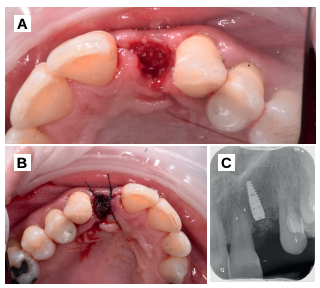

Se planificó la exodoncia del 2.2, para colocar un implante inmediato post-extracción, solicitando el consentimiento informado a la paciente. Una vez obtenido, se procedió a realizar un bloqueo anestésico mediante técnica infiltrativa con articaína al 4% con adrenalina 1:100.000 del nervio alveolar superior anterior, y nasopalatino. Se realizó la extracción forma atraumática y el fresado en una posición palatina, para favorecer la restauración implantosoportada posterior (Figura 5).

Tras la extracción, se separó en primer lugar la corona de la raíz, y se dividió la raíz en dos fragmentos, para poder retirar la gutapercha intrarradicular. Mediante el dispositivo Smart Dentin Grinder® (Kometa Bio. Bioner, España), se obtuvo un injerto con un tamaño de partícula de 300-1200 micrómetros, tras un tiempo de procesado total de 15 minutos (Figura 6).

Se colocó el injerto entre la superficie vestibular del implante, y la cortical vestibular, para cubrir el injerto con una esponja de fibrina (Gelatamp®) y dar dos puntos simples de sutura con poliamida no absorbible de 4/0 (Supramid®), realizando una radiografía periapical en el post-operatorio inmediato, para verificar la colocación adecuada del implante y del material de injerto (Figura 7). Así mismo, y con el objetivo de valorar el mantenimiento de la cortical vestibular se realizó un escáner de haz cónico realizado en el post-operatorio inmediato (Figura 8).

herida (B), radiografía periapical en el post-operatorio inmediato (C).

de dentina rellenando el gap.